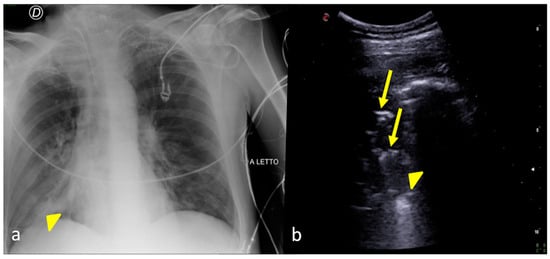

3. Confirming or Excluding Pneumothorax and Monitoring its Evolution

2. Characterizing and Monitoring Areas of Decreased Transparency on the CXR